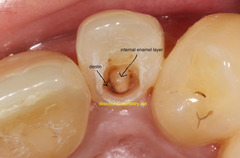

Inflamed pulp tissue within a tooth that is severely decayed or has a large open caries lesion a)gingival hyperplasia b)papillary hyperplasia of the palate c)epulis fissuratum d)chronic hyperplastic pulpitis-pulp polyp

Front

Chronic Hyperplastic Pulpitis- pulp polyp

Back